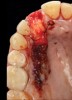

4. Facial and occlusal views of initial clinical presentation of tooth No. 8.

Figure 4

5. Facial and occlusal views of initial clinical presentation of tooth No. 8.

Figure 5